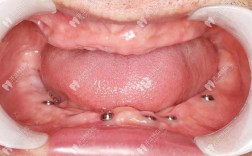

牙周植骨手术通常在局部麻醉下进行,医生首先会彻底清理病变的牙周组织,包括刮除牙根表面的牙结石、菌斑及病变骨质,随后根据骨缺损的类型和程度,选择合适的骨移植材料(如自体骨、异体骨、人工骨复合材料等)植入缺损区域,部分病例会覆盖生物膜(如胶原膜、膜引导组织再生膜)以促进骨再生,最后缝合牙龈切口,整个过程约1-2小时,术后患者需在观察室休息30分钟无异常后离院。

| 术后1-3个月 | 饮食:逐渐恢复正常饮食,但仍避免用术区咀嚼硬物(如坚果、骨头); 口腔卫生:可使用冲牙器(低压模式),清洁术区周边牙齿; 复查:术后1个月、3个月复查,拍摄X光片评估骨结合情况。 |

骨结合需3-6个月,期间牙齿可能轻微松动(非术区),若松动加重需警惕; 保持口腔卫生,每日刷牙2次(每次3分钟),使用牙线,预防牙周病复发; 若计划种植牙,需待医生确认骨结合良好后进行。 |

- 术后3个月:重点复查骨结合情况(植骨材料与自身骨融合程度),若为种植前植骨,医生会判断是否达到种植条件。